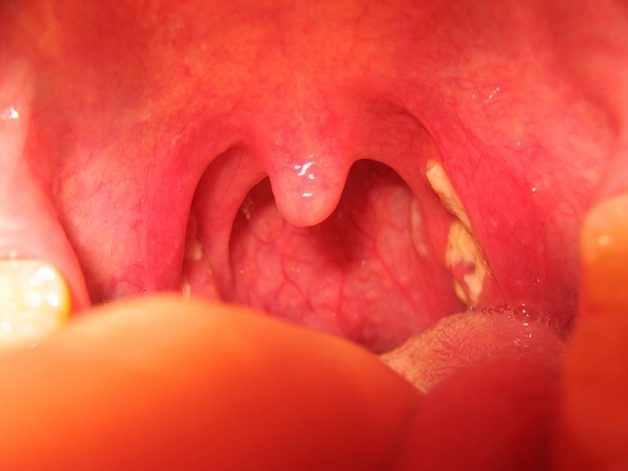

Phẫu thuật loại bỏ amidan chỉ được chỉ định cuối cùng khi bệnh không thể điều trị bằng phương pháp khác